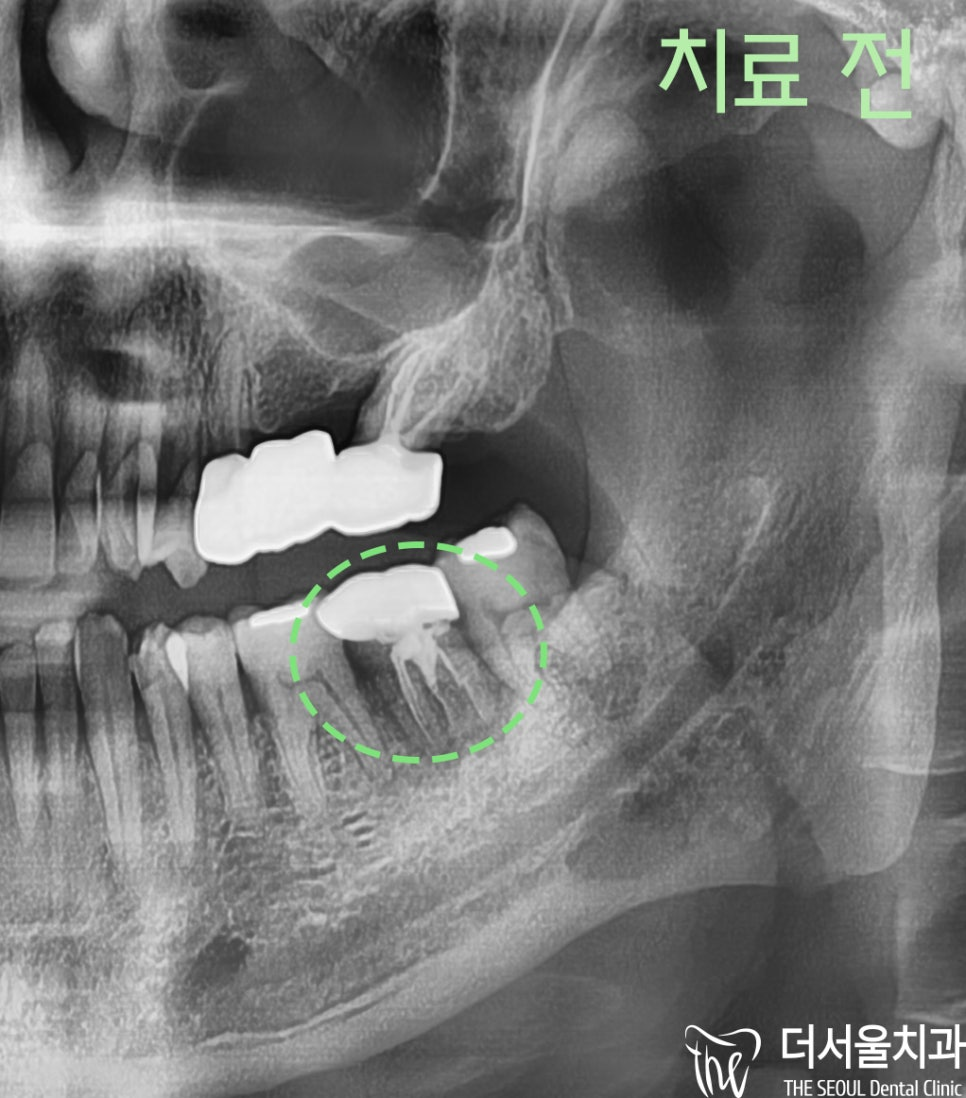

안녕하세요. 박현준 원장입니다. 제가 3년전에 적었던 글을 하나 보여드릴게요. (최근에 치료가 끝났거든요!) 이전 글의 내용을 정리하면 순서로 설명을 드렸었습니다.